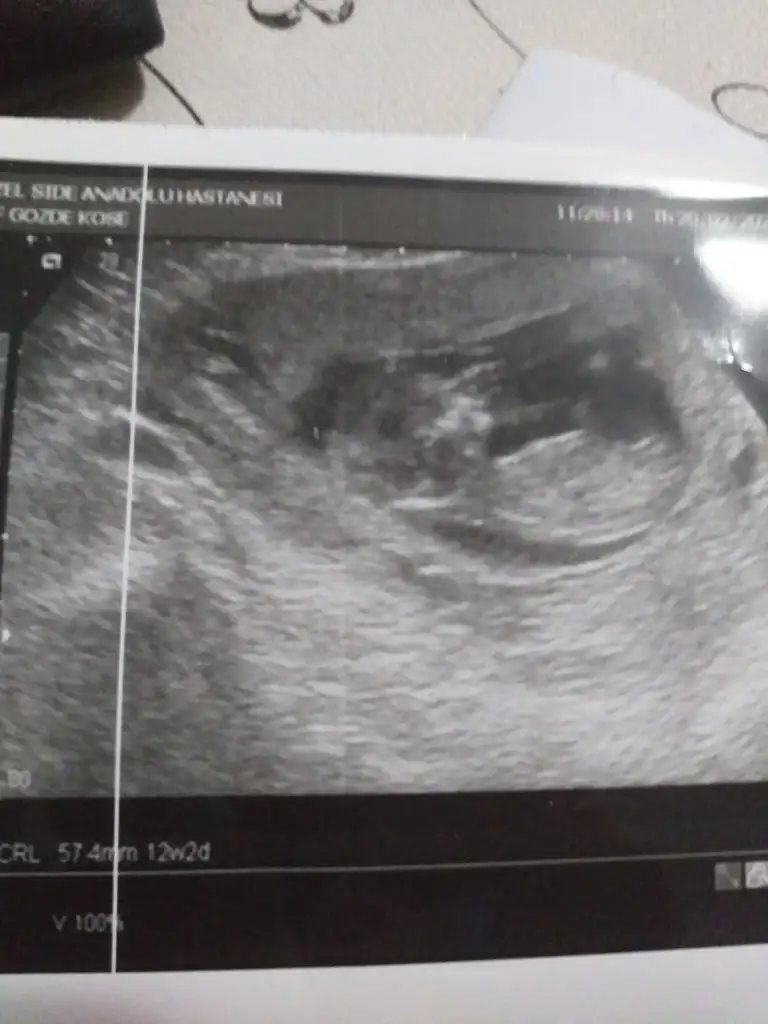

Banada bakarmısınız 12+2 günlükErkek ve kız için 11 yada 12 hafta usg görüntüsü olmalı açıklamalar asagıda yazıyorrabbim herkesin gönlüne göre nasip etsin inşallah .. ecmain

Net değil başka usg paylaşımBanada bakarmısınız 12+2 günlük

Kız gibi13 haftalık olduk sizce ne olabilir cinsiyeti çok çok merak ediyorum

Tamam çok teşekkür ederimmErkek gibi 12+ da paylaşın emin olamadım![]()

Sadece bunlar varNet değil başka usg paylaşım